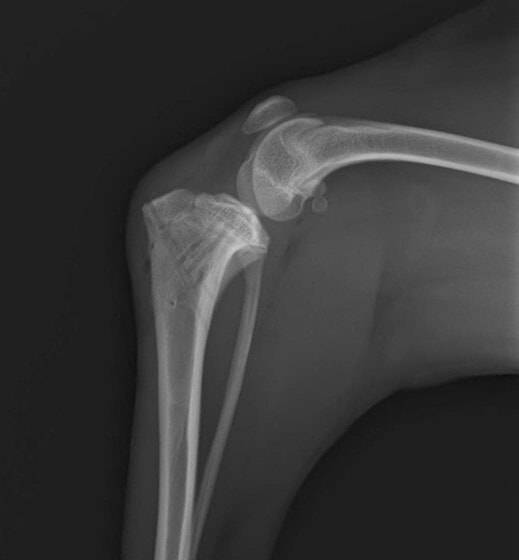

症例3:キルシュナーワイヤーのピンニングによる整復

ペルシャ猫 11ヶ月齢 雄

他院にて左大腿骨遠位の成長板骨折(salter-harrisⅠ型)が認められており、治療相談を目的として来院。当院にて、キルシュナーワイヤーを用いたピンニングにより骨折部位の整復を行いました。術後の経過は良好で、現在も経過観察中です。

術前レントゲン

術後レントゲン